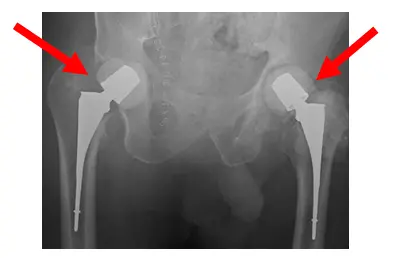

Láminas de control intraoperatorio. Las imágenes muestran la colocación del espaciador de cemento de ambas cabezas y cuellos femorales presumiblemente. Las radiografías muestran dosis altas de antibióticos espaciadores

La radiografía muestra la pelvis tras la colocación de cemento bilateral en la cadera. Las radiografías muestran espaciadores de cemento

Las radiografías muestran un espaciador bilateral de cadera sin aflojamiento ni fracturas pélvicas